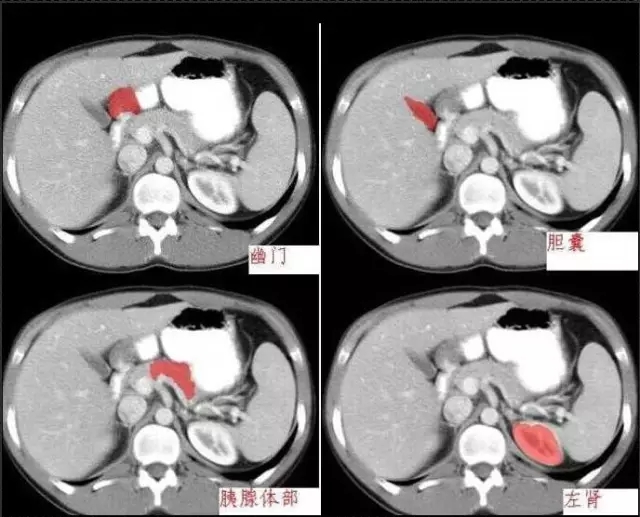

秒懂:腹部 CT 看這篇就夠